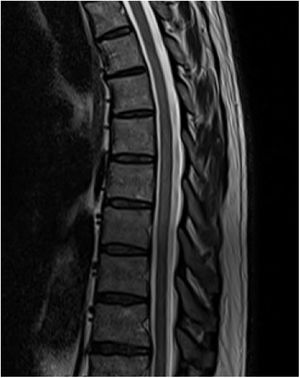

An MRI study (Figs. 1 and 2) revealed a slight signal alteration in the T6-T11 segments, with hyperintensity on T2-weighted sequences; the lesion did not present gadolinium uptake or mass effect. These findings are compatible with longitudinally extensive transverse myelitis of the thoracic spinal cord.